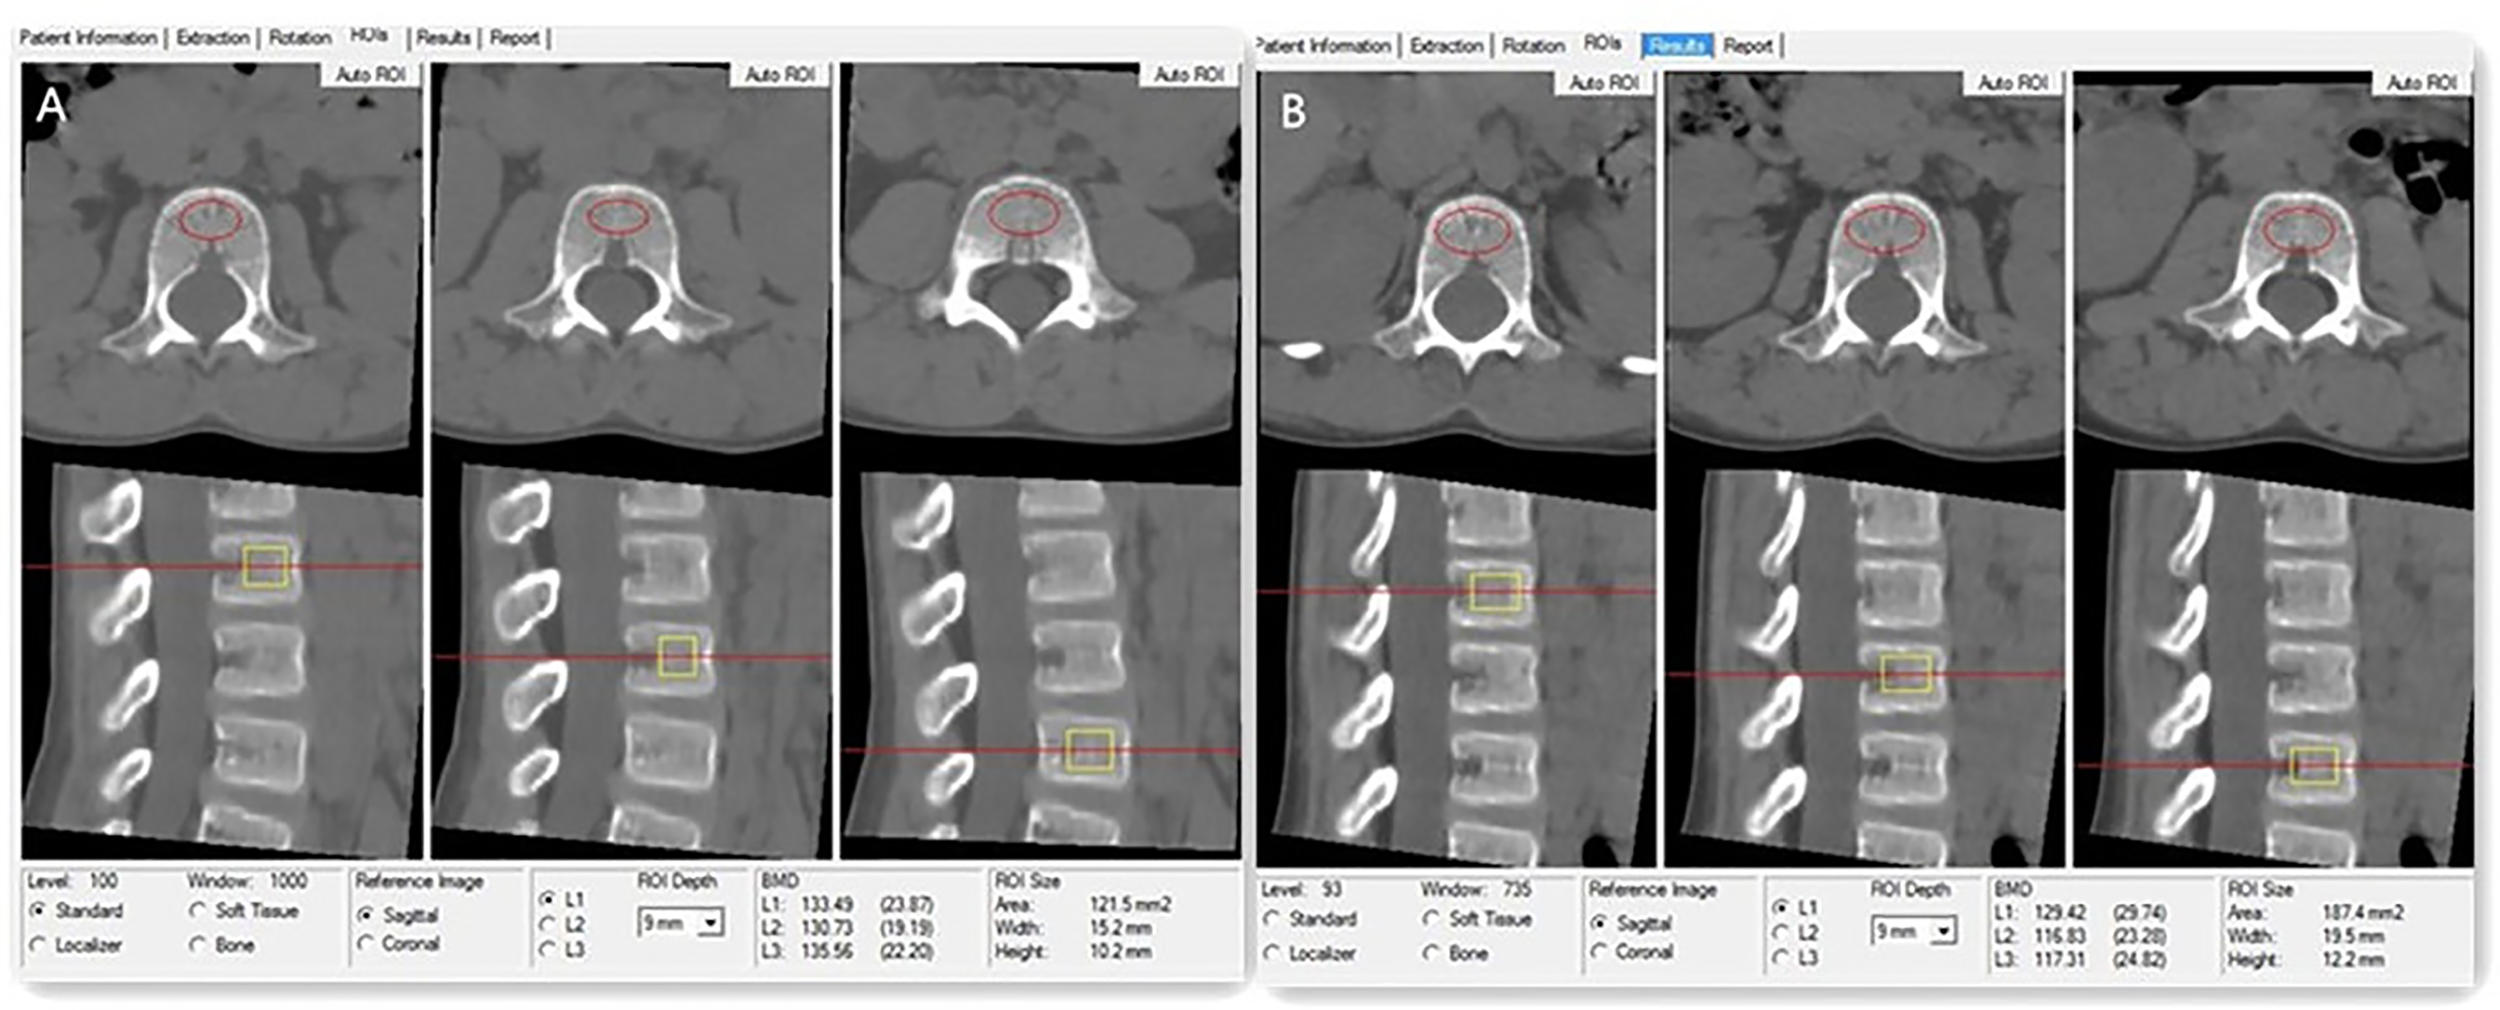

Asynchronous BMD calibration in combination with QCT Pro analysis software (Mindways Software, Inc.) was used to obtain lumbar spine (L1–L3) trabecular volumetric BMD (mg/cm3) (Figure 1), as previously reported (16). References for vertebral BMD Z scores based on age and sex were provided by the manufacturer of the QCT software (Mindways Software) (23). A low BMD was defined as a Z score of ≤ -2.0 according to the current ISCD recommendations for children (15). All patients or their families provided written informed consent to undergo QCT scanning.

Figure 1

(A) Images for a 7-year-old boy with DMD who has been treated with GC for 2 years. The measurements of L1, L2, and L3 vertebral trabecular volumetric bone mineral density (BMD) are shown. The BMD of L1, L2, and L3 is 133.49 mg/cm3, 130.73 mg/cm3, and 135.56 mg/cm3, respectively; the average lumbar volumetric BMD is 133.26 mg/cm3, and the Z score is -1.55. (B) The same boy with DMD was followed up after 1 year of GC therapy. The measurements of L1, L2, and L3 vertebral trabecular volumetric bone mineral density (BMD) are shown; the BMD of L1, L2, and L3 is 128.42 mg/cm3, 116.83 mg/cm3, and 117.31 mg/cm3, respectively. The average lumbar volumetric BMD is 121.19 mg/cm3, and the Z score is -1.97.